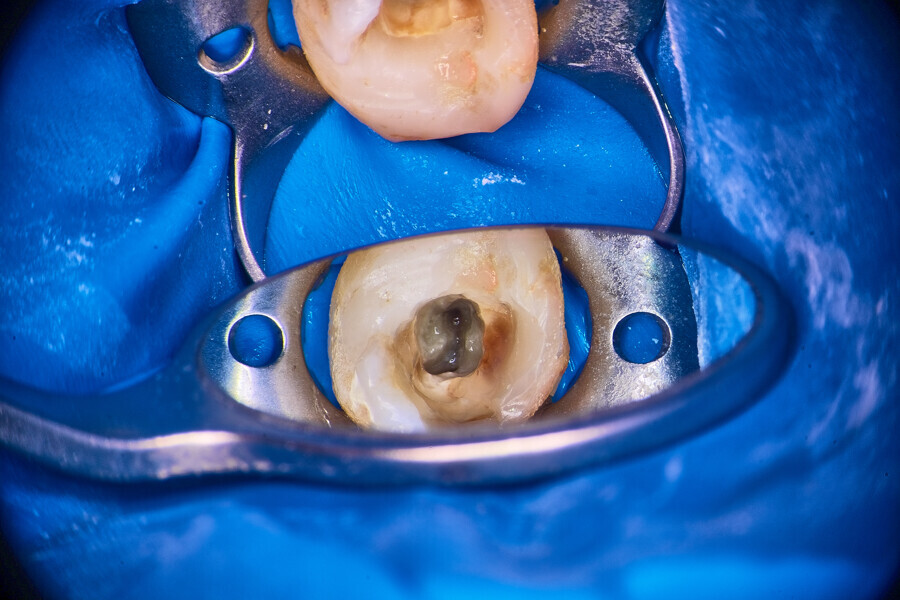

Under local anaesthesia, a dental dam was placed, and the field was sealed with liquid dental dam (RUBBER-DAM liquid, CERKAMED; Fig. 2). The temporary restoration was removed. The pulp chamber was irrigated with distilled water and sodium hypochlorite 5,25% activated with ultrasonic tips (Fig. 3). The first mesiobuccal (MB1), DB and palatal (P) canals were patent, so I was able to establish the working length with the C-PILOT file (VDW) and an apex locator (E-PEX, Eighteeth). The canals were shaped up to approximately two-thirds of the working length with the 25/0.07 Perfect Shape reciprocating file (Shenzhen Perfect Medical Instruments). The dentine above the orifice of the MB2 canal was removed using a diamond-coated ultrasonic tip (ED3D, Woodpecker), revealing an isthmus located between the MB1 and MB2 canals. Preparation of the orifice of the MB2 canal was possible only in the coronal third with a hand file (Fig. 4). The isthmus between both canals was removed for an additional 2 mm in depth also with the diamond-coated tips (Fig. 5).